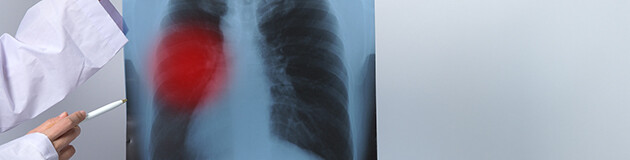

Mesothelioma is an extremely aggressive type of cancer in the respiratory system, and it is caused almost exclusively by asbestos. The earlier mesothelioma is diagnosed, the more likely it is to be treatable, so if you are in any way concerned, consult your doctor immediately.

Signs of asbestos-related disease can appear similar to other health conditions. Symptoms such as chest pain, shortness of breath and a chronic cough, for example, can be misdiagnosed, so if you have been exposed to asbestos, it's vital to let your doctor know

Asbestos-related disease is commonly associated with lung cancer, but peritoneal mesothelioma can also be caused by ingesting asbestos fibers. This form of mesothelioma accounts for less than 20% of all cases, with early symptoms including fluid build-up and abdominal swelling.